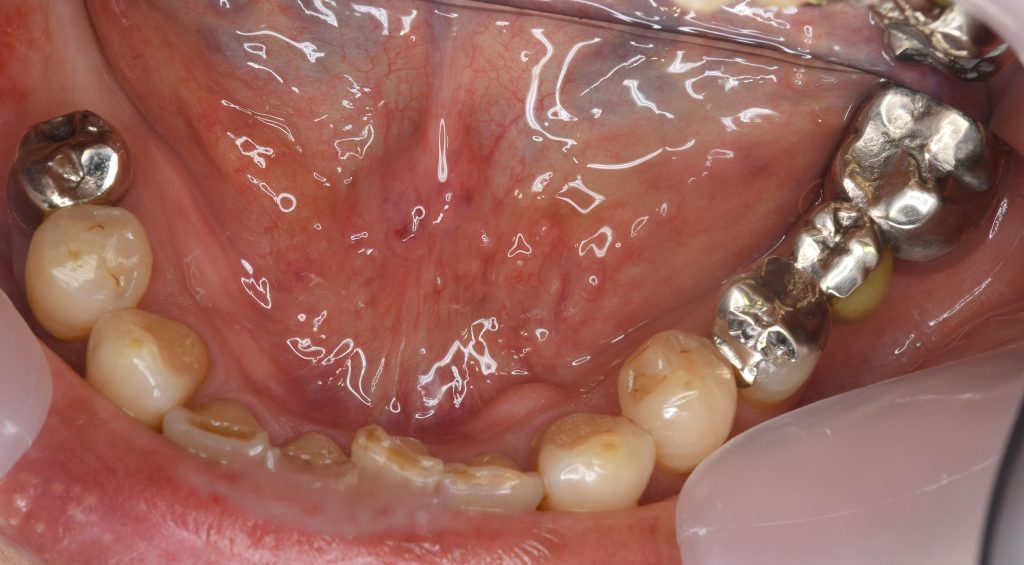

症例5入れ歯が煩わしい、奥歯でしっかり噛みたいという主訴で来院

治療前

治療後

主訴 一口腔に4個の部分義歯が装着されており、入れ歯が煩わしい、奥歯でしっかり噛みたい、インプラント希望され来院。

上顎の前歯、右側第二大臼歯、下顎右側第一大臼歯、第二大臼歯と、計4本のインプラントを埋入。

上顎前歯に関しては、抜歯後数十年経過の為に歯列弓が狭窄しており、骨造成、軟組織移植(CTG)を行い、歯肉のボリュームを回復。

術後約4ヶ月の免荷期間を経て、仮歯を装着、リハビリをし、最終補綴物を装着。

メリットは、複数の義歯から解放され、奥歯でしっかりと噛めるようになる。咀嚼機能の回復、向上。

デメリットは、外科的侵襲がある。治療期間が約3ヶ月かかる。保険外診療の為、経済的負担がある。

費用 220万(オペ・歯肉移植・人工骨・仮歯・最終補綴物まで含む)